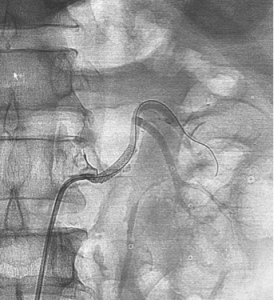

Bệnh nhân (BN) nam 53 tuổi, vào viện vì đau hông lưng trái đột ngột. Tiền sử: THA – rối loạn lipid máu điều trị không đều. Bệnh nhân đau hông lưng trái lan ra trước từng cơn 4 ngày, kèm tiểu buốt, tiểu máu, không sốt. Bệnh nhân nhập viện trong tình trạng da, niêm mạc bình thường, HA: 120/70mmHg, nhiệt độ 36,5 độ C, vỗ hông lưng (-), bụng mềm, các bộ phận khác không có gì đặc biệt. Xét nghiệm máu Ure 6,2 mmol/l, creatinin 155 µmol/l, AST/ALT 70/96 U/l, máu lắng tăng (giờ 1: 75mm, giờ 2: 87mm); nước tiểu có protein niệu, không có hồng cầu, bạch cầu; các xét nghiệm khác, siêu âm bụng, X quang phổi bình thường. BN được chỉ định chụp CT ổ bụng có tiêm cản quang, trên phim chụp CT bụng thấy hình ảnh hai động mạch thận trái, động mạch trước bể tách cao hơn và có hình ảnh bóc tách ở vị trí 1/3 giữa, có lòng giả, thành động mạch sau vị trí bóc tách dày do huyết khối trong thành, nhu mô 1/3 trên kém ngấm thuốc do thiếu máu, có vài ổ hoại tử không ngấm thuốc cản quang kích thước dưới 10mm (hình 1). Động mạch sau bể tách thấp hơn, thành mạch và lòng mạch bình thường, không có hình ảnh thiếu máu cực dưới thận. BN được điều trị nội khoa 3 ngày với Aspirin 81mg/ngày, clopidogrel (Plavix) 75mg/ngày, rosuvastatin (Crestor) 10mg/ngày, paracetamol 1g/ngày. Chụp mạch số hoá xoá nền động mạch thận cho thấy thấy hình ảnh tương tự với cắt lớp vi tính, điểm bóc tách của động mạch trước bể bắt đầu từ cách gốc 10mm, kéo dài khoảng 15 mm gây hẹp lòng thật, lòng giả còn lưu thông thuốc cản quang kích thước khoảng 3x2mm. Tiến hành can thiệp đặt một stent Biomine 4 x 19mm qua đoạn mạch thận tổn thương (hình 2). Sau đặt stent 1 ngày, BN không đau thắt lưng, không rối loạn tiểu tiện, thăm khám các bộ phận không thấy bất thường; xét nghiệm ure: 6,4 mmol/l, creatinin 115 µmol/l, AST/ALT 81/136 U/l, tổng phân tích nước tiểu bình thường. BN ra viện tiếp tục dùng clopidogrel/ aspirin (Duoplavin) 75/100mg/ngày, Crestor 10mg/ngày. Sau 1 tháng, BN tái khám, xét nghiệm ure 5,7mmol/l, creatinin 119 µmol/l, AST/ALT 36/56 U/L, hình ảnh chụp CT ổ bụng có tiêm cản quang thấy động mạch thận trái lưu thông tốt và Stent nở hoàn toàn, không thấy lòng giả, nhu mô thận thuộc vùng cấp máu của động mạch trước bể hồi phục gần hoàn toàn (hình 3).

![]() Hình 2: Đặt stent động mạch thận vị trí bóc tách |

![]() Đặt stent động mạch thận vị trí bóc tách |